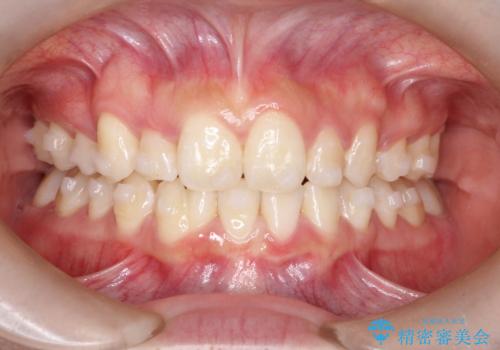

- 前歯の凸凹と口元の突出感を主訴に来院されました。

臼歯関係が上顎前突傾向のため、上の小臼歯を抜歯してワイヤー矯正を行なっております。

下顎の叢生はIPRを行なって配列しています。